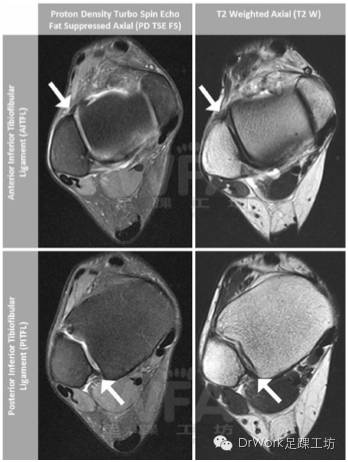

4.MRI

• 诊断AITFL断裂:灵敏度93%,特异性100%

• MR的诊断准确率更高

• 但亦有一定的假阳性率